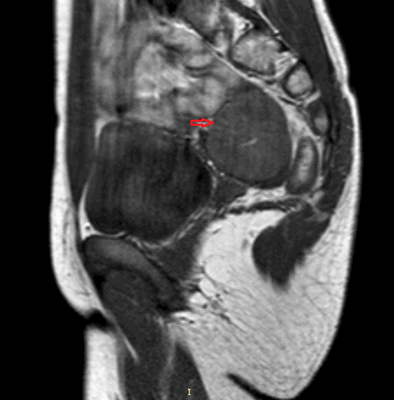

Рисунок 3. - тератома яичника а -УЗИ, б — МРТ.

- УЗИ. «Ультразвук» нужен для того, чтобы выявить первичный очаг как гонадной (в половых органах), так и внегонадной герминогенной опухоли. Его также проводят в ходе терапии, чтобы оценить ее эффективность.

- КТ (расшифровка: компьютерная томография), МРТ (расшифровка: магнитно-резонансная томография), ПЭТ-КТ (расшифровка: позитронно-эмиссионная томография, совмещенная с КТ). Эти обследования необходимы, чтобы рассмотреть структуры организма послойно и визуализировать опухоль. Они показывают, как сильно распространен патологический опухолевый процесс на находящиеся рядом ткани и органы, есть ли поражение костей. КТ - это самый чувствительный метод для обнаружения метастазов в легких. Проведение МРТ и КТ головного мозга необходимо, чтобы обнаружить и визуализировать герминогенные новообразования эпифиза.

Особенности течения заболевания определяются локализацией, размером и степенью злокачественности неоплазии. Типичными симптомами герминогенных опухолей яичника являются боли в животе различной интенсивности в сочетании с нарушениями менструального цикла. У детей последний признак отсутствует, что обуславливает отсутствие настороженности в отношении поражения внутренних половых органов на начальных стадиях заболевания. При прогрессировании герминогенных опухолей к перечисленным симптомам присоединяются увеличение живота и нарушения мочеиспускания. При пальпации на начальных стадиях определяется округлый, умеренно подвижный узел с четкими контурами. В последующем узел увеличивается в размере, возникают увеличение и деформация живота. На поздних стадиях выявляется асцит и нарушения функций различных органов, обусловленные отдаленным метастазированием.